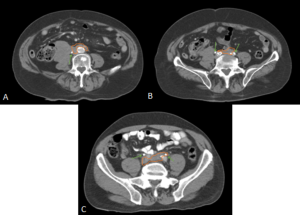

MAGNETIC RESONANCE IMAGING (MRI)

MRI offers superior soft-tissue contrast and enables non-contrast visualisation of the renal collecting system, making it particularly valuable in patients with renal impairment.

RPF is typically hypointense on T1-weighted images with variable intensity on T2-weighted images as well as in apparent diffusion coefficient values depending on the degree of active inflammation [2,3].